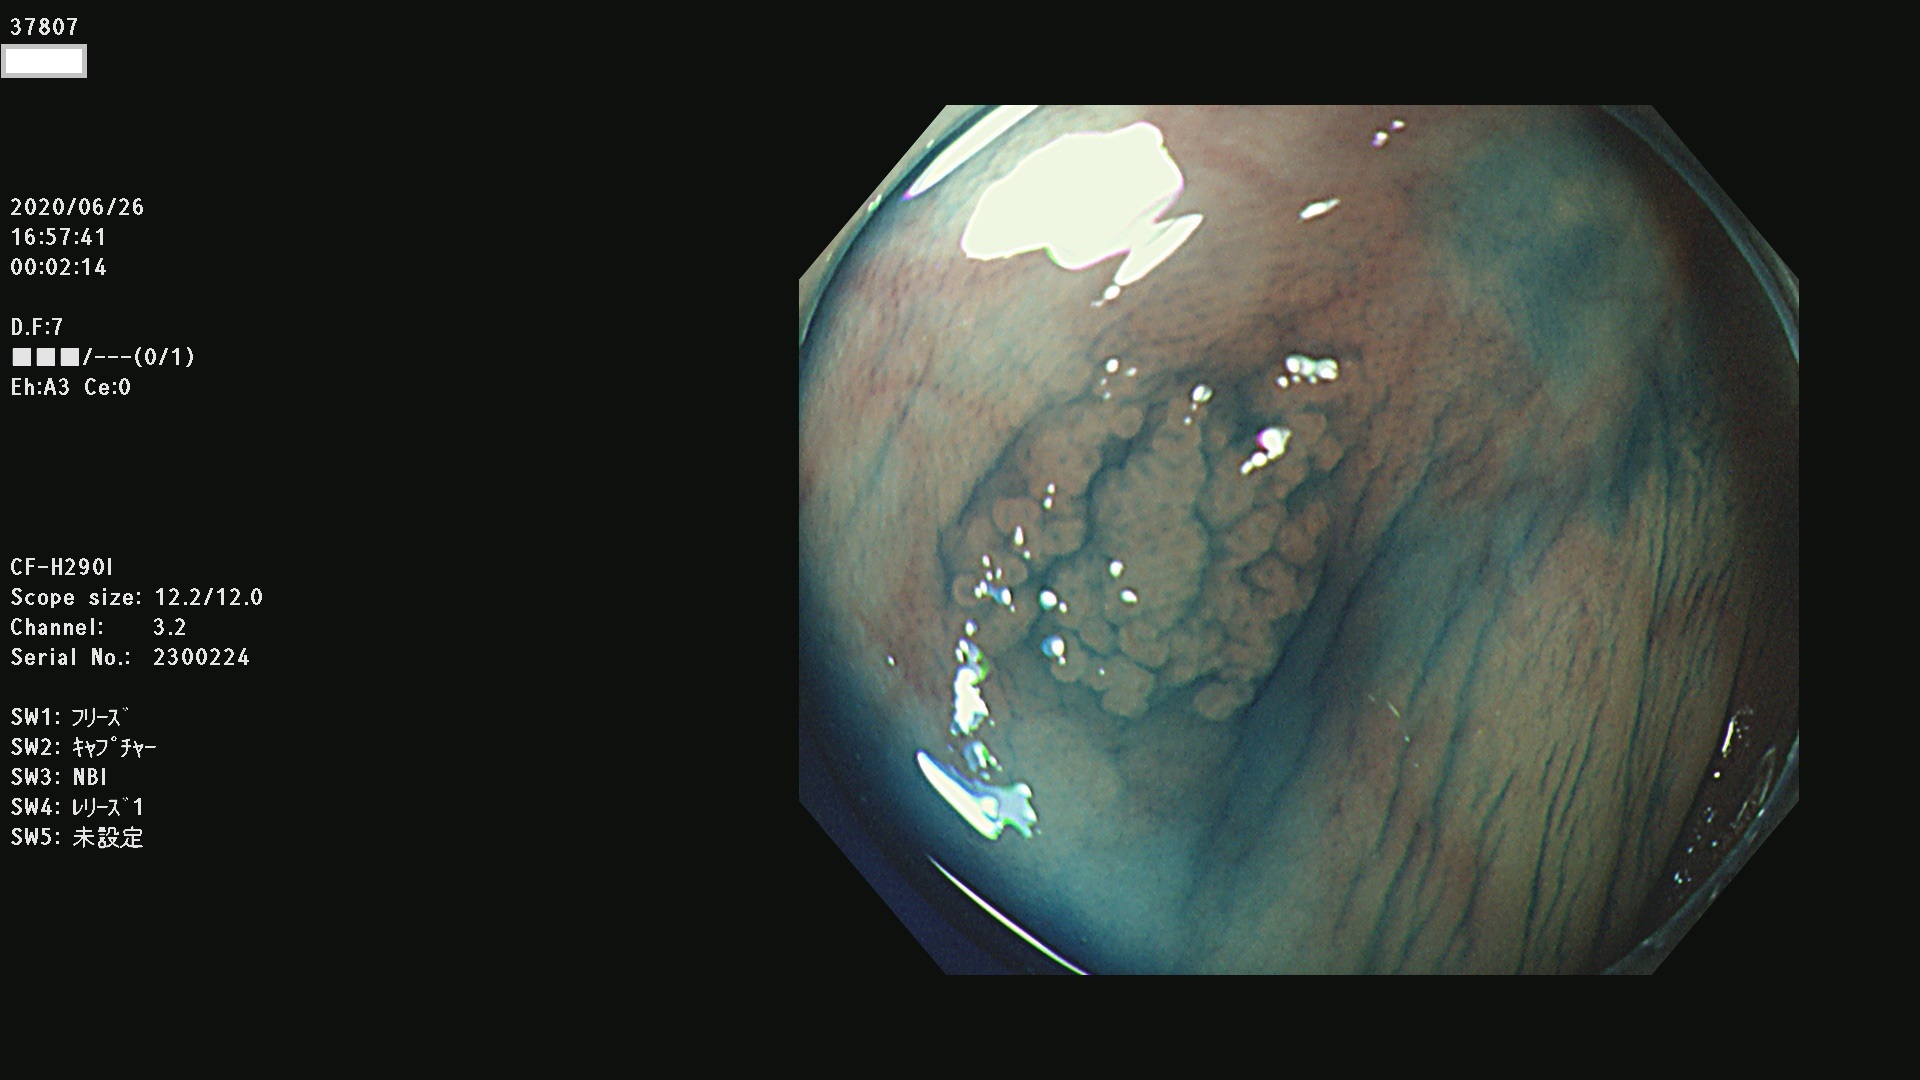

腺腫発見率 75 % (カルテ番号 37800〜37899の100名の方の検査結果で集計)大腸癌検診最新情報

以下のカルテ番号の方に腺腫(Adenoma,Group3〜5)が見つかりました(集計法)

37800(SSAPのみ) 37801 37802 37803 37804 37805 37806 37807 37808 37809(SSAPのみ) 37810 37811 37812 37813 37814 37815 37817 37818 37819 37820 37821 37822 37824 37825 37826 37827 37828 37829 37832 37833 37836 37837(SSAPのみ) 37839 37840 37842 37844 37845(SSAPのみ) 37847 37849 37850 37851 37852 37853(SSAPのみ) 37855 37856 37857 37860 37861 37862 37863 37864 37867 37868 37871 37874 37876 37877 37879 37880 37881 37882 37883 37886 37887 37888 37889 37890 37891 37892 37893 37894 37896 37897 37898 37899

発見困難で危険性の高い平坦型病変(上記100名より抽出) ![]()